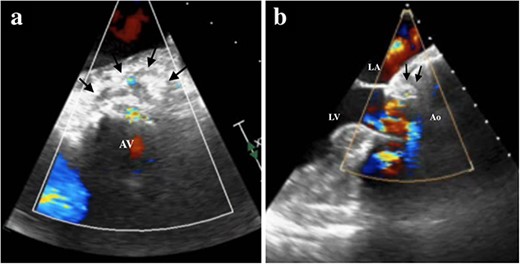

Under light sedation and local anesthesia, a 26-mm SAPIEN 3 valve was deployed with 1.5 ml less balloon inflation to avoid excessive pressure on the aortic annulus. After valve deployment, TTE revealed a small pericardial effusion. Pericardial drainage was performed, and blood was drained. Intraoperative angiography revealed a small amount of contrast leakage around the ascending aorta (Fig. 2). Transesophageal echocardiography (TEE) under deep sedation revealed a hematoma at the aortic annulus with blood inflow (Fig. 3a and b). Emergent open surgery was performed. The aorta was exposed through a median sternotomy. Cardiopulmonary bypass was established via the ascending aorta and the right atrium, and the aorta was cross-clamped. Antegrade cardioplegia was administered via an aortic root cannula, and cardiac arrest was achieved without complications. The prosthetic valve was firmly adherent to the aortic annulus and carefully removed. A tear in the non-left coronary commissure was sutured using 5–0 Prolene (Fig. 4). An INSPIRIS 21 mm valve (Edwards Lifesciences, Irvine, CA, USA) was implanted. The patient was discharged on postoperative day 14 after rehabilitation. One year after surgery, TTE revealed no paravalvular leakage and a preserved ejection fraction of 34%.

TEE showing the hematoma around the ascending aorta and blood flow at the hematoma at 0 degrees of view (a, arrows), at 120 degrees of view (b, arrows). LA, left atrium; LV, left ventricle; Ao, aorta; AV, aortic valve.